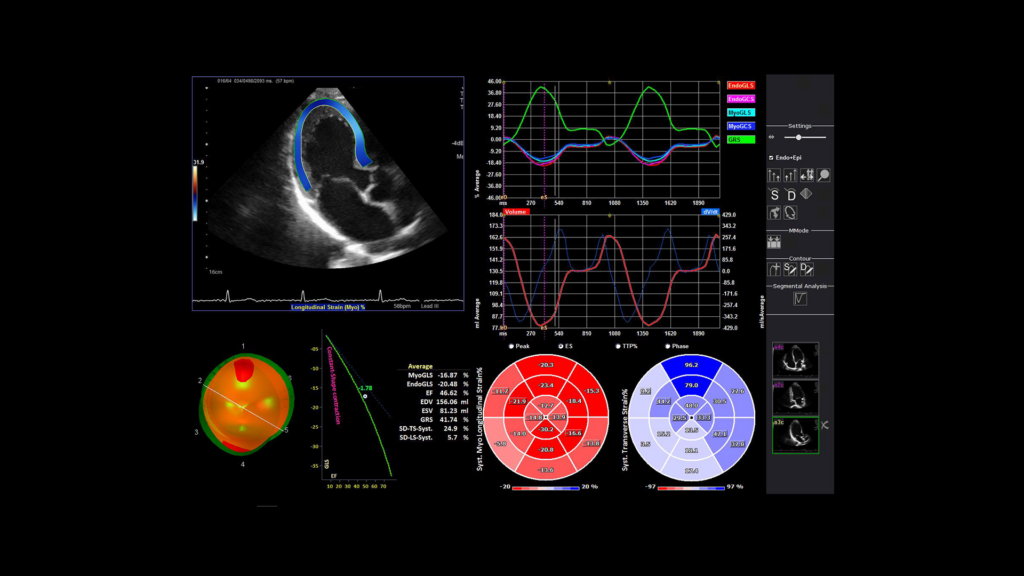

- Bệnh lý cơ tim: khảo sát đánh giá sự vận động các thành tim giúp chẩn đoán trong bệnh lý nhồi máu cơ tim, bệnh cơ tim phì đại, giãn nở.

Siêu âm tim đánh dấu mô (Nguồn: Internet)